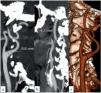

Material and methodsIn total 300 patients who had supra-aortic computed tomography angiography (CTA) were enrolled in this study from 2015 to 2021. The study groups consisted of 100 ischemic stroke patients, 100 patients with intracranial aneurysms, and 100 control subjects. The intracranial aneurysm patient group was divided into two subgroups according to the presence of subarachnoid hemorrhage (SAH). The largest diameters of the ICA C1 (cervical) and C2 (petrous) segments in all individuals were measured bilaterally on CTA images. The ICA diameter ratios of the cases were measured using the formula C1-C2C1. The relationship between the age and ICA vessel analysis was evaluated as well.

ResultsThe mean ICA bulb width values in the ischemic stroke patient group and the intracranial aneurysm patient group were significantly higher than the control group (p < 0.001). The ICA C1 and C2 segment diameter values and ICA diameter ratio were smaller in the intracranial aneurysm patients with SAH than those who had not (p = 0.7). There was a statistically significant but weak relationship between the age and ICA diameter ratios in all study groups (R-squared value of 0.26, p = 0.03).